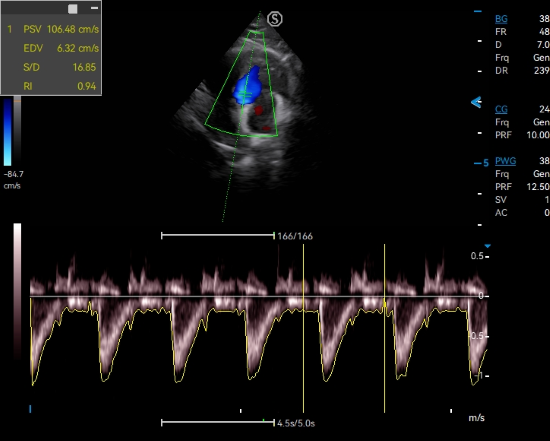

Triplex integrates anatomical imaging, dynamic flow observation and spectral analysis for a comprehensive assessment on vascular disease from multiple perspectives. PW auto correlation being activated during triplex on is to help present another real time quantitative analysis.

PW mode provides accurate hemodynamic and spectral information to detect subtle changes in blood flow and enable quantitative measurement.

CW mode sensitively detects and visualizes high-velocity blood flow signals, which is helpful for the diagnosis of early vascular disorders in animals.